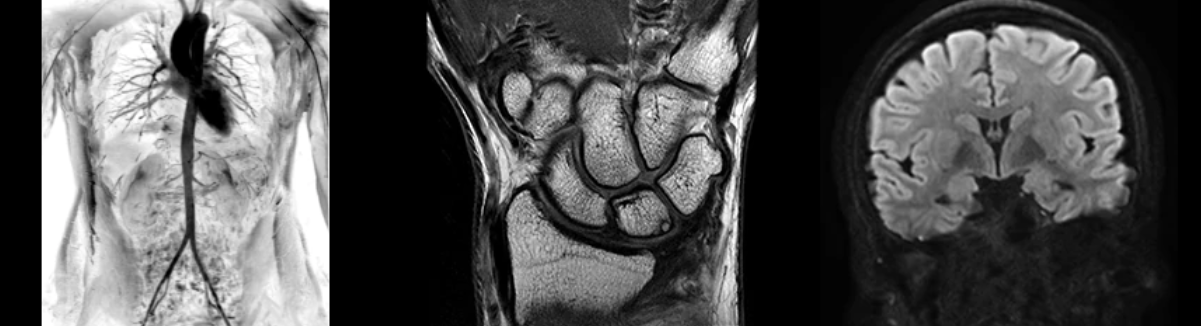

Клинические приложения, полностью соответствующие вашим потребностям

- NeuroWorks

Представляет собой универсальное решение для визуализации анатомии головного мозга, позвоночника, сосудов и периферических нервов с четкой дифференциацией тканей.

- OrthoWorks

Программное решение OrthoWorks разработано для визуализации структур опорно-двигательного аппарата с прекрасным контрастированием тканей.

- BodyWorks

Используйте BodyWorks для визуализации абдоминальной и тазовой областей с учетом любых типов пациентов.

- OncoWorks

Включает клинические приложения для обработки и визуализации анатомических и морфологических данных, специфичных для каждого типа онкологических образований.

- CVWorks

Приложение для кардиовизуализации, с помощью которого вы сможете получить данные о морфологии, динамике кровотока, функции миокарда, а также информацию о структуре сосудов.

- PaedWorks

Набор специализированных протоколов, позволяющих без усилий удовлетворять потребностям самых маленьких и уязвимых пациентов.